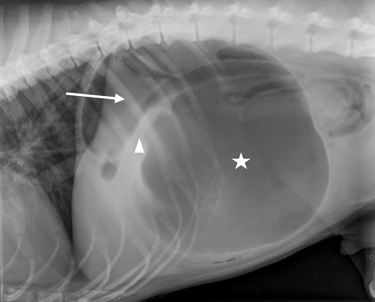

Case 2 - Captain (Case report)

Gastric dilatation and volvulus with partial splenectomy – German Shepherd Dog, 7y, male neutered